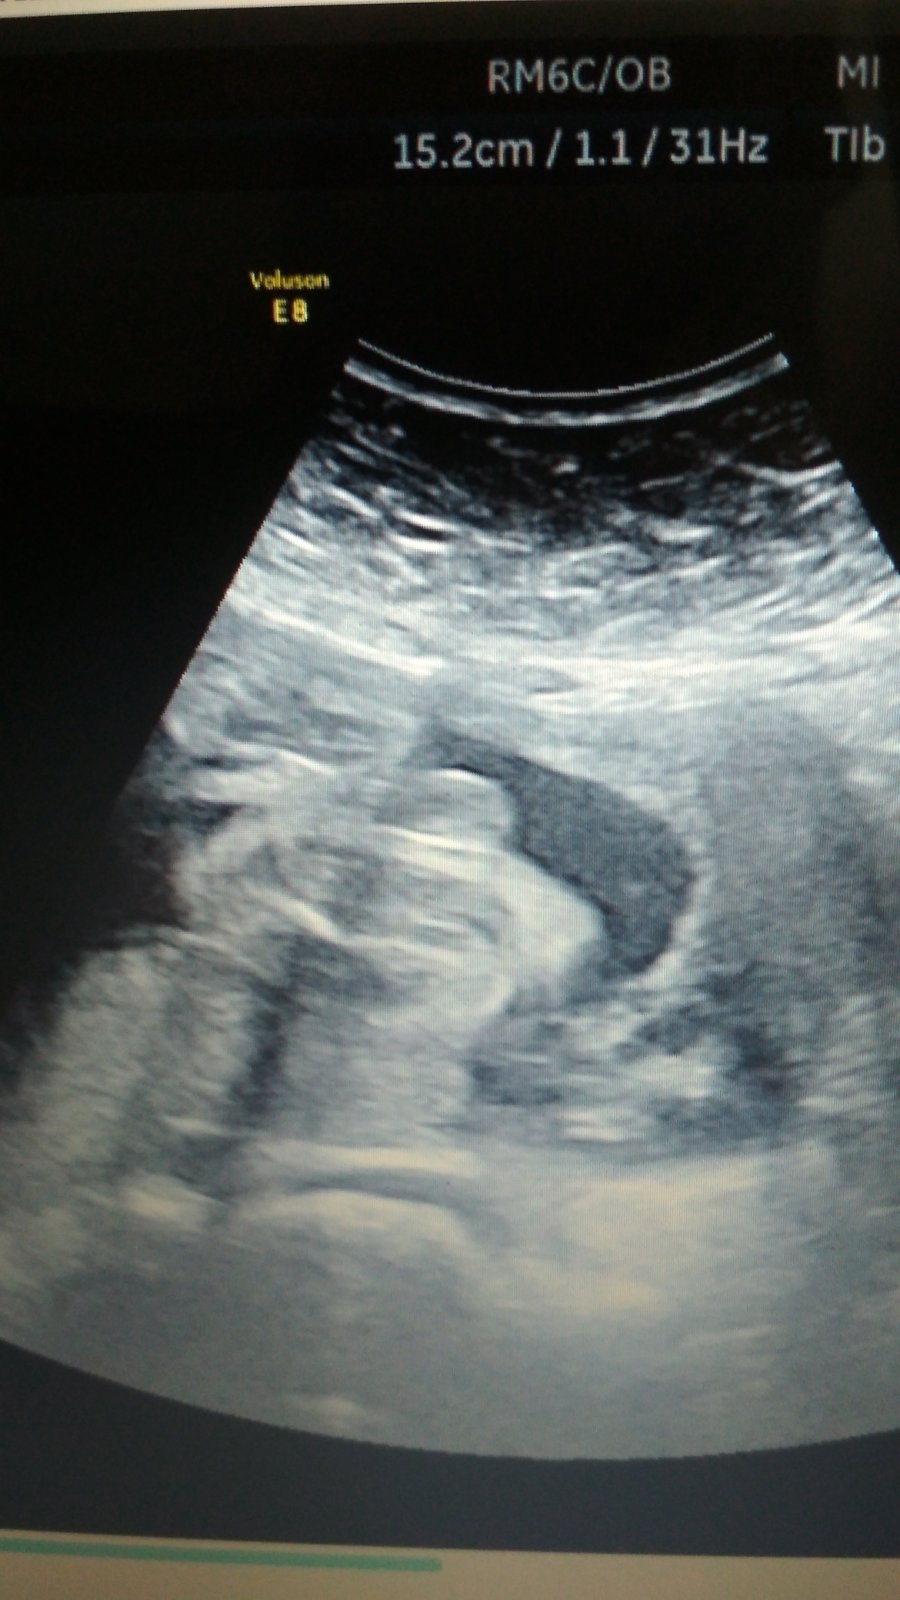

Holky, co vidíte? Kluk nebo holka?

@cysticka no je to foto rozkroku,nevim zda tam jsou steheni kosti a kostrc a na druhe strane pipinka.Uz mam doma 2 kluky a ty to meli jine 😂

Preju ti tu holcicku, ale ta pipka na utz by mela vypadat na kavovy zrno. Tohle mi prijde jako kulicky 🙂

U nás taky hodně lidí nelékařů tipovalo kluka podle této mojí fotky (moji doktoři mi to řekli až tak v 34tt, bylo to s nimi komplikované, chtěli megasuperhyper VIP poplatky)... no a máme princeznu 🙂 Takže zatím nezoufej, třeba to holka bude 🙂 Z fotky se to obecně hůř pozná než třeba z videa, jsou tam různé stíny, průřezy apod.

@zouzalka1982 určitě dej vědět. Všichni říkali, že u holčiček je vidět kávový zrno. No, u té mojí mi to zrno ani při troše fantazie nepřipomíná. Ale holčička to nejspíš opravdu bude. Už mi ji od cca 16tt řekli 3 doktoři. Nikde nic netrci, tak to snad bude. Jistota samozřejmě bude až po porodu.

Já bych teda řekla, ze holčička, pipinku vidim🤔Každopádně držím palecky. Mám doma 2 kočky a utz byl hodně podobný tvému.